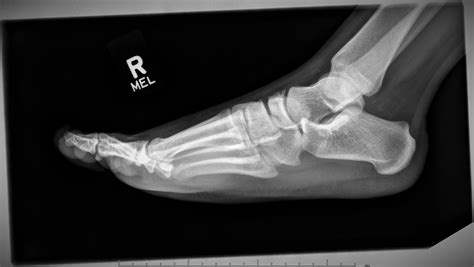

X-ray Imaging Primary scan to identify major breaks or displacement.

MRI or CT Scan Used for occult fractures that are hidden on standard X-rays.